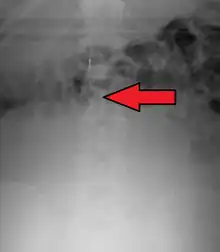

Placement

IVC filters are placed endovascularly, meaning that they are inserted via the blood vessels. Historically, IVC filters were placed surgically, but with modern filters that can be compressed into much thinner catheters, access to the venous system can be obtained via the femoral vein (the large vein in the groin), the internal jugular vein (the large vein in the neck) or the arm veins with one design. Choice of route depends mainly on the number and location of any blood clot within the venous system. To place the filter, a catheter is guided into the IVC using fluoroscopic guidance, then the filter is pushed through the catheter and deployed into the desired location, usually just below the junction of the IVC and the lowest renal vein.[44]

Review of prior cross-sectional imaging or a venogram of the IVC is performed before deploying the filter to assess for potential anatomic variations, thrombi within the IVC, or areas of stenoses, as well as to estimate the diameter of the IVC. Rarely, ultrasound-guided placement is preferred in the setting of contrast allergy, chronic kidney disease, and when patient immobility is desired. The size of the IVC may affect which filter is deployed, as some (such as the Birds Nest) are approved to accommodate larger cavae. There are situations where the filter is placed above the renal veins (e.g. pregnant patients or women of childbearing age, renal or gonadal vein thromboses, etc.). Also, if there is duplication of the IVC, the filter is placed above the confluence of the two IVCs [45] or a filter can be placed within each IVC.[46]